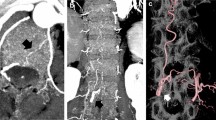

In 6 out of 24 cases, bypass close to bone in source images of DEBR-CTA was erroneously misclassified as bone so that affected voxels were set to −1024 HU by the DEBR algorithm (Fig. 2). Thus, in these cases the DEBR algorithm had a negative effect on vessel integrity with an apparent discontinuity of vessel in source images mimicking focal stenosis with “pseudo-gaps” in MIP images (Fig. 3). Without a priori knowledge of erroneous misclassification, these “pseudo-gaps” were significant as they affected rating for visualization of bypass segment TS compared to gold standard DSA.

Source images of CTA and DEBR-CTA. a The CTA source image without bone removal shows EC/IC bypass adjacent to bone (closed arrow) when crossing the site of craniotomy (TS segment). b Focal erroneous misclassification of bypass close to bone (open arrow) in the corresponding CTA source image with DE bone removal

“Pseudo-lesion” in DEBR-CTA. “Pseudo-lesion” in maximum intensity projection of CTA with dual energy bone removal (b; open arrow): apparent focal bypass stenosis due to misclassification of vessel close to bone was verified as patent normal appearing bypass in DSA and CTA source images without bone removal (a, b; closed arrows)